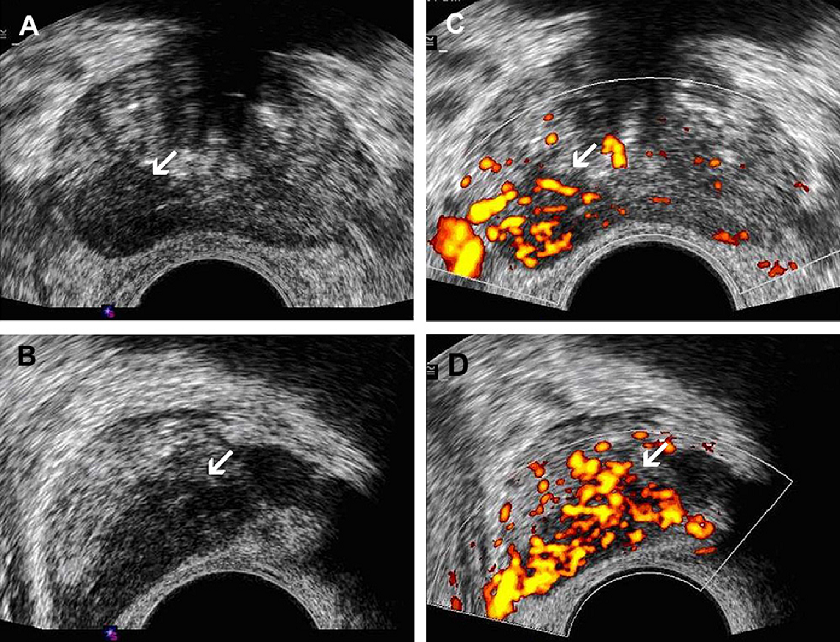

Злокачественная опухоль предстательной железы. Злокачественные новообразования простаты. Генная терапия злокачественных опухолей. Генная терапия в онкологии Карцинома предстательной железы УЗИ. Допплерография предстательной железы. Онкология предстательной железы

Карцинома предстательной железы УЗИ. Допплерография предстательной железы. Онкология предстательной железы Злокачественное новообразование предстательной железы. Карцинома предстательной железы. Susp BL предстательной железы что это. Tumor предстательной железы

Предстательная железа MRT. Мультипараметрическое мрт предстательной железы. Предстательная железа кт норма. Аденома предстательной железы мрт Гистосканнинг предстательной железы. Трансректальная биопсия предстательной железы под контролем УЗИ. Ангиография предстательной железы. Лимфоузлы в предстательной железе

Гистосканнинг предстательной железы. Трансректальная биопсия предстательной железы под контролем УЗИ. Ангиография предстательной железы. Лимфоузлы в предстательной железе Фиброз предстательной железы. Объемное образование предстательной железы. Склероз в предстательной железе

Карцинома 4 степени предстательной железы. Онкология предстательной железы. Опухоль предстательной железы стадии Эластография предстательной железы. Компрессионная эластография предстательной железы. УЗИ С эластографией предстательной железы. Образование предстательной железы УЗИ

Эластография предстательной железы. Компрессионная эластография предстательной железы. УЗИ С эластографией предстательной железы. Образование предстательной железы УЗИ Опухоль предстательной железы. Злокачественное новообразование предстательной железы. Карцинома предстательной железы. Tumor предстательной железы

Предстательная железа у мужчин. Представительна яжелеза. Опухальпредседательнойжелезы Трансректальное УЗИ предстательной железы. УЗИ трузи предстательной железы. Карцинома предстательной железы УЗИ. Опухоль предстательной железы УЗИ

Трансректальное УЗИ предстательной железы. УЗИ трузи предстательной железы. Карцинома предстательной железы УЗИ. Опухоль предстательной железы УЗИ Массажер для аденомы простаты. Массаж предстательной железы мужчинам

Образование предстательной железы УЗИ. УЗИ предстательной железы РПЖ. Диагностика опухолей предстательной железы

Образование предстательной железы УЗИ. УЗИ предстательной железы РПЖ. Диагностика опухолей предстательной железы Злокачественное новообразование предстательной железы. Онкозаболевания предстательной железы. Аденома простаты злокачественная. Мкб предстательной железы